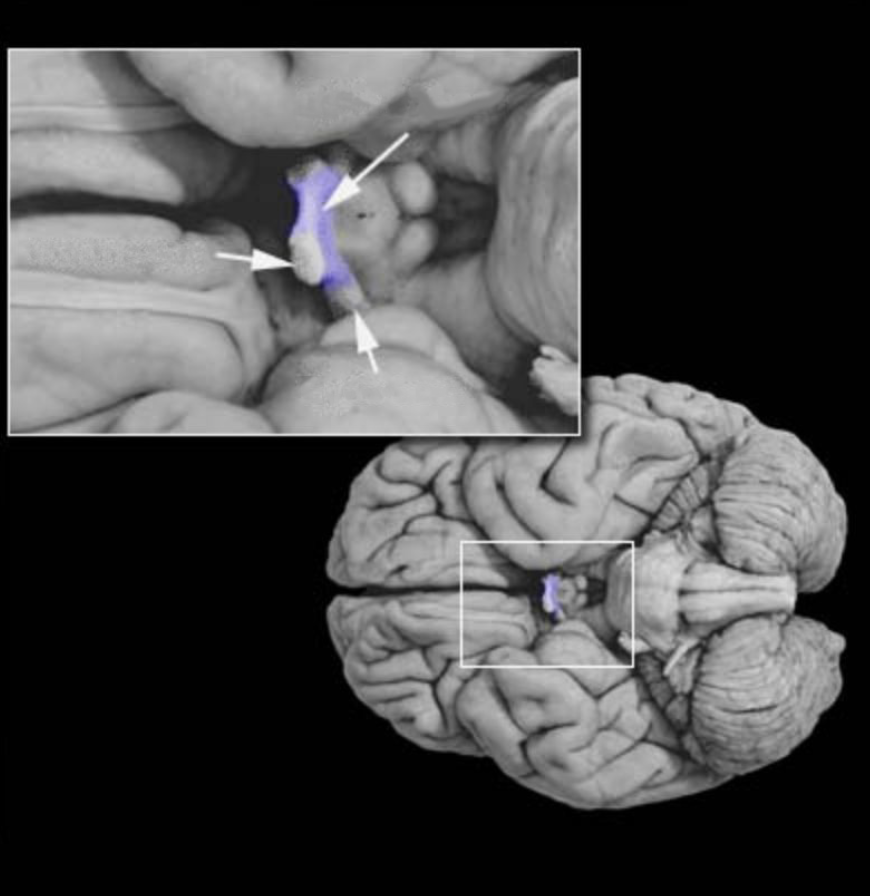

Optic chiasm

White matter structure formed by the partial decussation of the optic nerves. contains the axons of retinal ganglion cells in the nasal parts of each retina that project across the midline to contralateral diencephalic and mesencephalic targets. Caudal to the optic chiasm, these axons join other axons from the temporal retina to form the optic tract.